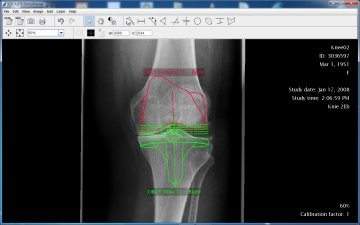

LOCALITE OrthoPlanner® - Digitale Prothesenplanung

Der LOCALITE OrthoPlanner ist eine Planungssoftware für den Einbau von Endoprothesen, die auf digitalen Röntgenbildern basiert. Die Software bietet die Möglichkeit, Endoprothesenimplantate beliebiger Gelenke und aller Prothesenhersteller zu planen. Winkel, Abstände und Größen können exakt gemessen und das Planungsergebnis archiviert werden. Röntgenfilmausdrucke und durchsichtige Plastikschablonen werden daher überflüssig.